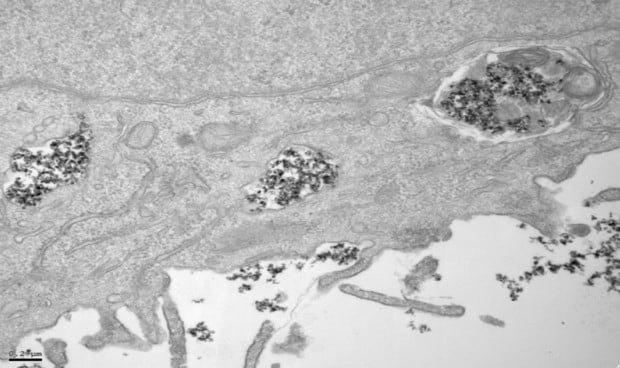

El hecho de introducir en células nanopartículas de óxido de hierro permite que se liberen fármacos de forma localizada, eliminando las células tumorales a través de la emisión de calor o para llevar a cabo diagnósticos en resonancias magnéticas. Para lograr la aprobación clínica se debe conocer al detalle cómo se comportan dentro de las células, y el estudio ha logrado revelar que la respuesta a este aspecto se encuentra en la cobertura de las nanopartículas.

Portilla también ha querido añadir que “en las células tumorales las nanopartículas se acumulan en endolisosomas, donde se degradan más lentamente, mientras que en las células macrofágicas del entorno tumoral, la degradación ocurre más o menos rápidamente dependiendo del recubrimiento, ya que en función de este se acumulan en vesículas con diferente capacidad de degradación. Estos hallazgos son de vital importancia a la hora de diseñar las nanopartículas ya que podremos, en función de su futura aplicación, potenciar el efecto deseado dependiendo de la diana terapéutica”.